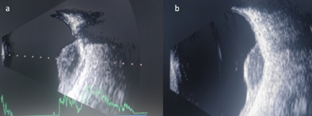

An 18-year-old female, presented with sudden diminution of vision since 7 days in left eye. The best corrected visual acuity in right eye was 20/20 and left eye was 20/100 on Snellen’s chart. On examination anterior chamber and vitreous was quiet, disc was within normal limits with a yellowish white subretinal mass with small hemorrhage on the surface along the inferior arcade up to mid periphery measuring 12DD(disc diameter) (Figure 1) with presence of SRF involving the macula and the inferior quadrant was noted. The b-scan showed mild vitreous echoes with a dome-shaped choroidal lesion with a dimension of 6.82x14.50mm, with no surface reflectivity irregular low-to-medium internal reflectivity with the presence of an anechoic space in the mass, suggestive of an inflammatory etiology (Figure 2). Complete physical examination and medical evaluation findings, including a chest x-ray film, were normal. Results of a blood uveitis workup (serum angiotensin converting enzyme, serum lysozyme, Venereal Disease Research Laboratory titer, Toxoplasma titer, Toxocara titer) were negative. A purified protein derivative skin test was highly positive (induration, 20X20 mm). Optical coherence tomography showed subretinal fluid (SRF) at macula (Figure 3). We made the clinical diagnosis of solitary choroidal tuberculoma in an immunocompetent patient in whom routine investigations failed to identify systemic tuberculosis infection. The patient was started on isoniazid, rifampin, and ethambutol for a 6-month period. Under supervision of a physician, systemic steroids (1 mg/kg/day) in tapering doses were given. The choroidal granuloma subsequently decreased in size (Figure 1A‒C) (Figure 2B) over the following 3 months to form a flat chorioretinal scar. After 3 months of oral ATT and steroids, no improvement in visual acuity (20/100) was noted due to persistent SRF at macula (Figure 3B), intravitreal triamcinolone acetonide 2 milligram was planned and resulted in complete resolution of the SRF at macula (Figure 3C) with shrinkage of the choroidal lesion at 4 month (Figure 1D,E).The final visual acuity was 20/20 and was maintained till 1 year follow up.

Figure 2 (A) b-scan ultrasonography showed mild vitreous echoes with a dome-shaped choroidal lesion with a dimension of 6.82x14.50X 5.5mm, with irregular low-to-medium internal reflectivity with the presence of an anechoic space in the mass. (B) b-scan at 1 month shows decrease in the size of granuloma (4.50 x11x 3.5mm), with clearing of the central anechoic space.

TB is caused by Mycobacterium tuberculosis, commonly described as a systemic disease that involves not only the lungs, but many other organs, including the eye. Ocular TB is a rare(1% of all cases of TB), can involve any part of eye and can occur with or without evidence of systemic TB. Large solitary granuloma is a common presentation and are present as a solitary yellowish or grayish white large lesion, generally located in the posterior pole.1 Diagnosis of TB requires microbiological confirmation and as this can be challenging in ocular tissue or fluids, evidence of systemic tuberculosis not only contributes to the diagnosis of presumed ocular tuberculosis but also provides specimens for microbiological and histopathological confirmation.2 Ultrasonography in granuloma shows low to moderate internal reflectivity, making it difficult to distinguish them from amelanotic malignant melanoma. The presence of an anechoic space in the mass points toward an inflammatory etiology.3 A thorough systemic evaluation, including radiographic studies is needed to detect other involved sites. Visual prognosis may be guarded but visual recovery in choroidal tuberculoma depends on involution to a flat inactive scar and can occur with proper and rapid diagnosis with early initiation of treatment depending on the location and size of the tuberculomas.3 Systemic treatment with the first-line combination regimen comprising isoniazid, rifampin, pyrazinamide, and ethambutol for a total of 6–12 months has been accepted as standard therapy.4 In the present case, a favorable response to treatment was demonstrated by the shrinking of the tuberculoma with oral ATT and steroid therapy, but visual gain was documented after treating with triamcinolone acetonide which resulted in resolution of the SRF and shrinkage of the granuloma. This case highlights a rare clinical scenario wherein choroidal tuberculoma is the presenting sign of TB. Ophthalmologists should be aware that solitary choroidal tuberculoma can occur in immunocompetent individuals. It is believed that ultrasonography is an easy and practical method for not only suspecting the diagnosis but also monitoring disease evolution and response to treatment. This is the first case which highlights the use of intravitreal triamcinolone acetonide in management of choroidal tuberculoma.